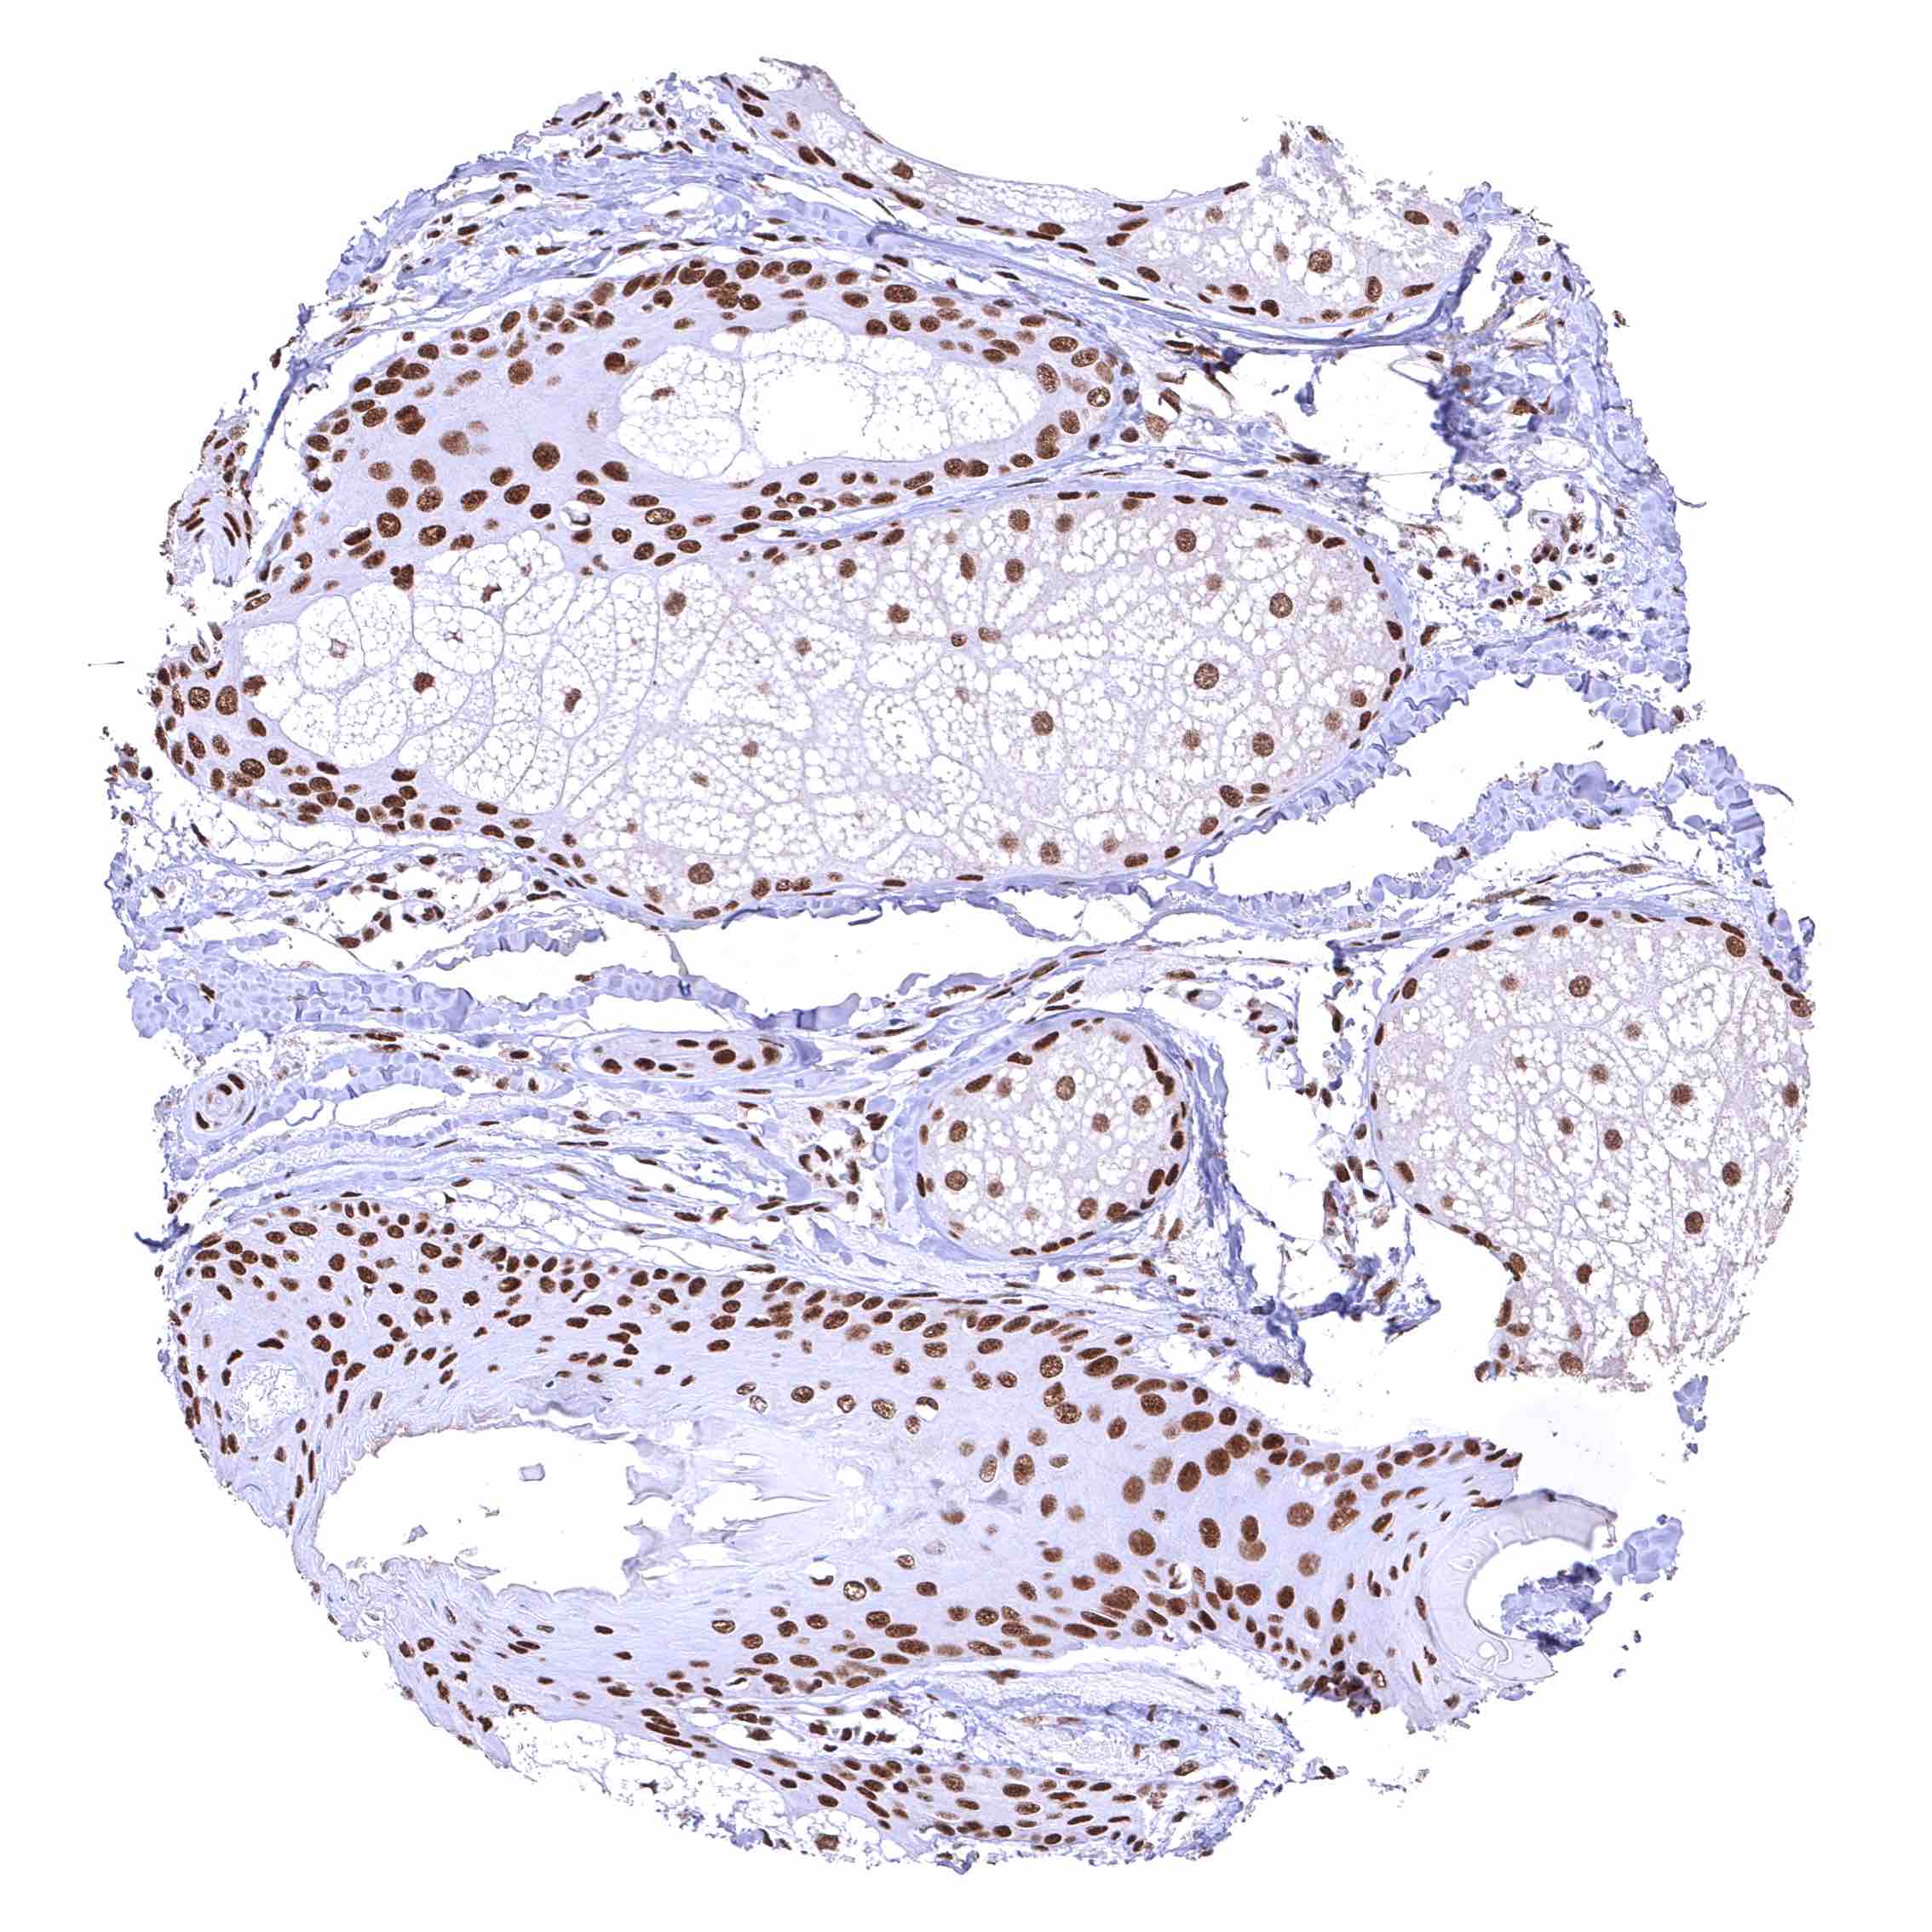

Uterus, ectocervix – Distinct nuclear BRD4 staining of squamous epithelial cells with a slight decrease of the staining intensity towards the most superficial cell layers.